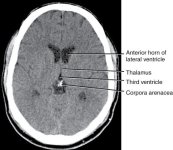

"The pineal gland is a mineralizing tissue. Its calcified concretions range from a few micrometres to several millimetres in diameter. ... It is generally agreed that the blood-brain barrier restricts the passage of fluoride into the central nervous system. The human pineal gland is outside the blood-brain barrier. It is one of a few unique regions in the brain (all midline structures bordering the third and fourth ventricles) where the blood-brain barrier is weak. Cells in these regions require direct and unimpeded contact with blood. Therefore, pinealocytes have free access to fluoride in the bloodstream. This fact, coupled with the presence of HA [hydroxyapatite], suggest that the pineal gland may sequester fluoride from the bloodstream. ... In conclusion, this study presented evidence that fluoride readily accumulates in the aged pineal."[11]

"The pineal gland is a mineralizing tissue. Its calcified concretions range from a few micrometres to several millimetres in diameter. ... It is generally agreed that the blood-brain barrier restricts the passage of fluoride into the central nervous system. The human pineal gland is outside the blood-brain barrier. It is one of a few unique regions in the brain (all midline structures bordering the third and fourth ventricles) where the blood-brain barrier is weak. Cells in these regions require direct and unimpeded contact with blood. Therefore, pinealocytes have free access to fluoride in the bloodstream. This fact, coupled with the presence of HA [hydroxyapatite], suggest that the pineal gland may sequester fluoride from the bloodstream. ... In conclusion, this study presented evidence that fluoride readily accumulates in the aged pineal."[11]